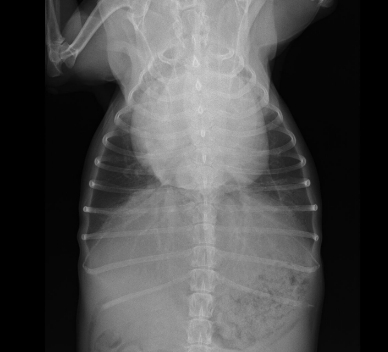

胸部X線検査(心臓の大きさや肺の状態の評価)

■心臓レントゲン 正常